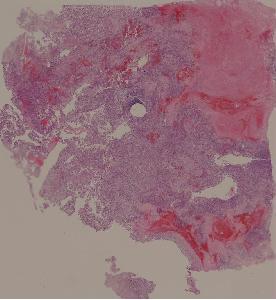

36.恶性淋巴瘤